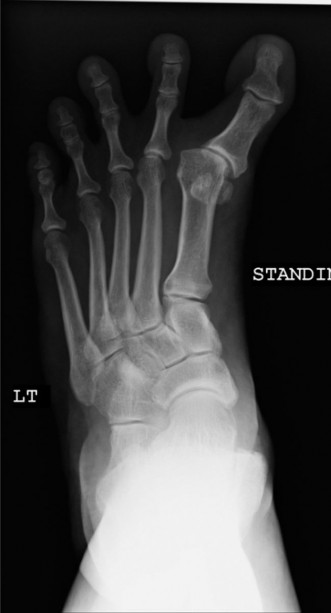

Standard weight-bearing radiographs are essential for evaluating bony alignment and joint pathology.

1. Weight-Bearing Anteroposterior (AP) View:

* Hallux Valgus Angle (HVA): Although the name implies valgus, in varus, this angle is negative (medial deviation of the proximal phalanx from the first metatarsal axis).

* Intermetatarsal (IM) Angle: Measure the angle between the first and second metatarsals. An overcorrected IM angle (often excessively small or even negative) can indicate a medial shift of the first metatarsal head.

* Distal Metatarsal Articular Angle (DMAA) / Proximal Phalangeal Articular Angle (PPAA): Assess the orientation of the articular surfaces. A medial inclination of the metatarsal head articular surface can contribute to varus.

* Sesamoid Position: Note the position of the medial and lateral sesamoids relative to the first metatarsal head. In varus, the medial sesamoid may be displaced medially, and the lateral sesamoid may be absent (post-excision) or also displaced medially if the toe is severely pronated.

* Joint Congruity: Evaluate for MTP joint subluxation or degenerative changes.

* Presence of Hardware: Identify any previous osteotomy fixation and assess its position and integrity.